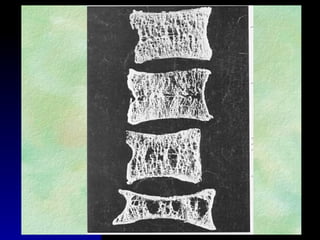

Pérdida de 10% de masa ósea en vertebra y en cadera, ^R de

Fx en 2 y 2.5 veces respectivamente.

Tercer tema RESISTENCIA OSEA NationalInstitutes of HealthNational Institutes of Health ConcensusConcensus Development Conference Statement .March 27-29, 2000Development Conference Statement .March 27-29, 2000  PICO DE MASA ÓSEAPICO DE MASA ÓSEA  PÉRDIDA DE MASAPÉRDIDA DE MASA ÓSEAÓSEA  ARQUITECTURAARQUITECTURA  RECAMBIO ÓSEORECAMBIO ÓSEO MICROFRACTURASMICROFRACTURAS  MINERALIZACIÓNMINERALIZACIÓN DENSIDAD ÓSEA 70% CALIDAD ÓSEA 30%